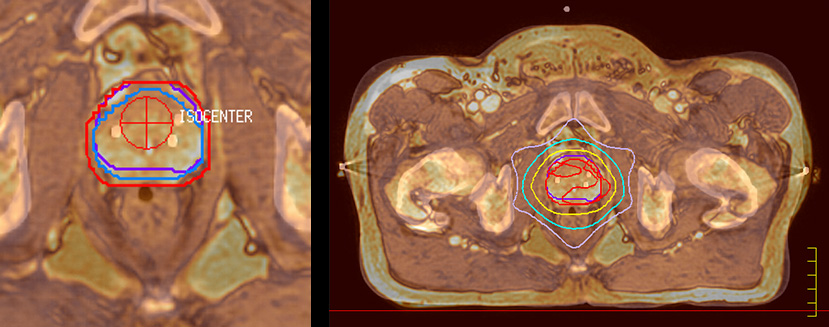

“When a patient registers, first CT simulation and MR simulation are done, followed by CT-MR registration on Pinnacle3. Then the target and normal organ delineation is performed on MR images. Meanwhile we create a reference CT image for online treatment and localization correction. During the treatment phase we can perform additional MRI scans to visualize the anatomy changes and create an adaptive plan. This plan basically adapts the treatment plan to the changes.” “Along with its great benefits, MR has introduced some new challenges,” Dr. Stevens says. “Radiation therapy teams generally have no experience with MR. The Philips training helped us to implement fully the things we can do with the Ingenia MR-RT system. So the training, as well as having a good MR physicist, is critical.”

“The biggest problem for CT-based planning, especially in prostate, is you can’t see the cancer very well,” says Dr. Stevens. “On CT it can be quite challenging to see the edge of the prostate especially at the apex. When the edge of the prostate can’t be delineated well on CT, radiation oncologists will increase their margins a little bit so they don’t miss it, but that can also increase toxicity.” “Using MR, the prostate is well delineated. We quickly see the edges of cancerous tumors like in prostate cancer, and as normal structures can be defined, we can optimize the treatment plan to protect these organs and their normal function. This can potentially improve the outcome. And it improves workflow as well. We can contour more quickly, confident that the tumor is going to be in the field.” “The Ingenia 3.0T MR scanner provides high resolution allowing us to make scans fast for the patients. It also gives the potential to include methods like MR spectroscopy and diffusion weighted Imaging, which we’re in the process of doing right now,” Dr. Stevens adds.

“There are some general challenges in RT imaging – even with CT – such as imaging geometry and positioning accuracy. Positioning is extremely important in RT, because we need reproducibility between imaging and treatment position. We also need accurate geometry so we can be sure our treatment plan is properly delivered during the treatment,” says Dr Yan. “The Ingenia MR-RT configuration includes an external laser positioning system for patient alignment and a flat tabletop for imaging the patient in treatment position. Ingenia MR-RT also came with a special QA package for regular monitoring of precision. Our Ingenia 3.0T scanner achieves good geometric accuracy – within a millimeter for most patients – and the phantom measurement is even better,” he adds. “Ingenia’s wide 70 cm bore is valuable to easily accommodate immobilization devices needed in RT,” says Dr. Stevens. “With a small bore MR scanner you can’t get the RT immobilization devices into the scanner properly; the large bore makes it easy to image patients in their immobilization device.”